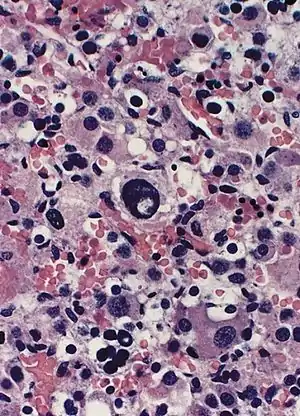

| Adrenal gland: Beckwith-Wiedemann syndrome Nuclear enlargement and hyperchromasia with nuclear "pseudoinclusion" near the center of field. Mitotic figures were not identified. | |

- Cytomegaly of the fetal adrenal cortex (pathognomonic)

Originally, Dr. Hans-Rudolf Wiedemann (born 16 February 1915, Bremen, Germany, died 4 August 2006, Kiel) coined the term exomphalos-macroglossia-gigantism (EMG) syndrome to describe the combination of congenital abdominal wall defects as hernia (exomphalos), large tongues (macroglossia), and large bodies and/or long limbs (gigantism). Over time, this constellation was renamed Beckwith–Wiedemann syndrome following the autoptical observations of Prof. John Bruce Beckwith (born 18 September 1933, Spokane, Washington),[32] who also observed a severe increase in the size of the adrenal glands in some of these patients.